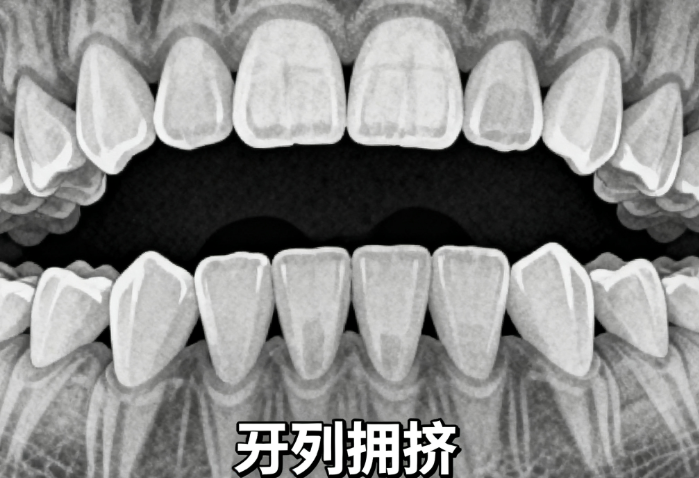

你是否曾经听说“戴牙套会变脸”?牙齿矫正真的会让下巴后移、甚至出现双下巴吗?90%的人都误解了!其实,牙齿矫正与下巴形态之间的关系远比想象中复杂。正畸治疗不仅可以改善牙齿排列和咬合,还可能对下巴线条产生积极影响。但若操作不当或存在骨性问题,也可能出现下巴后移甚至双下巴的现象。本文将深入解析牙齿矫正与下巴后移、双下巴的关系,帮你揭开真相。

牙齿矫正是否会导致下巴后移或双下巴,取决于多个因素,包括矫正方式、个体骨骼结构、年龄阶段等。

然而,如果患者的下颌骨发育不足(即骨性后缩),单纯正畸治疗可能无法改变骨骼结构,仅能改善表面形态。因此,是否会导致下巴后移或双下巴,要具体情况具体分析。